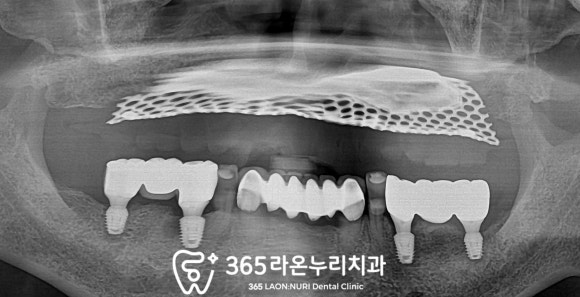

■ 3. 아래 어금니 조정 및 완성

위에 틀니를 사용하면서

implant에 적응하실 수 있게 임시 제작을 해드리고

불편한 것은 없으신지 모두

체크를 하고 보철을 올려드렸습니다.

아무리 픽스처를 잘 식립했다 하더라도

하부에 보철이 들어가면 어색함이

나타날 수 있기 때문에

여러 번 조정하면서 진행했습니다.

기존 틀니랑 안 맞으면

임플란트를 해야 되는 걱정이 있으셨는데

생각보다 편하고 저작도 잘 돼서

만족하고 사용하고 계신다 합니다.^^